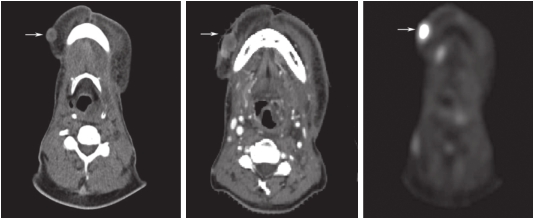

2017-01-24在我院CT检查:下颌体右前份皮下软组织结节影,大小约1cm×1cm(图1)。

2017-02-07全身PET-CT检查:右后上口颊、右侧口底、右侧下颌体右前份皮下软组织结节影,代谢增高,最大SUV值13.8,多系肿瘤转移(图1)。

图1 右侧下颌体右前份皮下软组织结节影(平扫CT,增强CT和PET-CT)